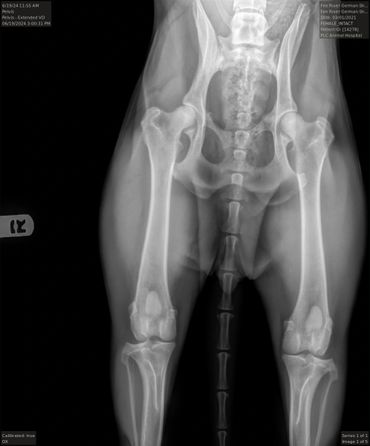

Hips (SV): Normal

PennHIP: L: 0.19. R: 0.33.